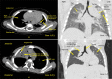

Figure 8

Figure 8. Case 1 (a) HRCT Axial scan chest in mediastinal window, (b) Coronal HRCT scan chest in lung window showing areas of collapse with atelectasis noted in apico-posterior and anterior segments of left upper lobe with mild volume loss of left upper lobe with mild upward displacement of left oblique fissure. Case 2 (c) Postoperative axial HRCT scan of chest in mediastinal window showing mild fluid density areas with internal few small air foci noted in apical and anterior area adjacent to first and second intercostal space right side. There are few internal radiopaque surgical clips noted, (d) Postoperative coronal HRCT scan of chest in lung window showing stapler occluding right upper lobar bronchus. There are areas of adjacent sub-segmental collapse noted.

HRCT - High-resolution computed tomography; P - Patient Image Credit: Dr. Dharmendra B. Parmar